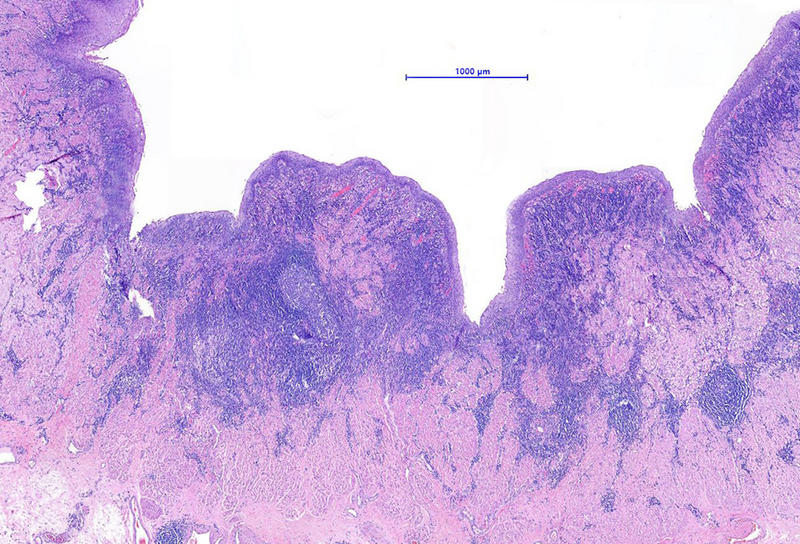

The microscopic examination of the resection specimen revealed diffuse lymphoplasmacytic infiltration throughout the oesophageal wall, with multiple lymphoid follicles and accentuation within the inner half (Panel A). On high magnification, diffuse infiltration of the overlying squamous epithelium by lymphocytes („lymphocytic oesophagitis pattern of injury”) and occasional plasma cells was observed (Panel B). The plasma cells were strongly positive for IgG and IgG4 (Panels C-D).